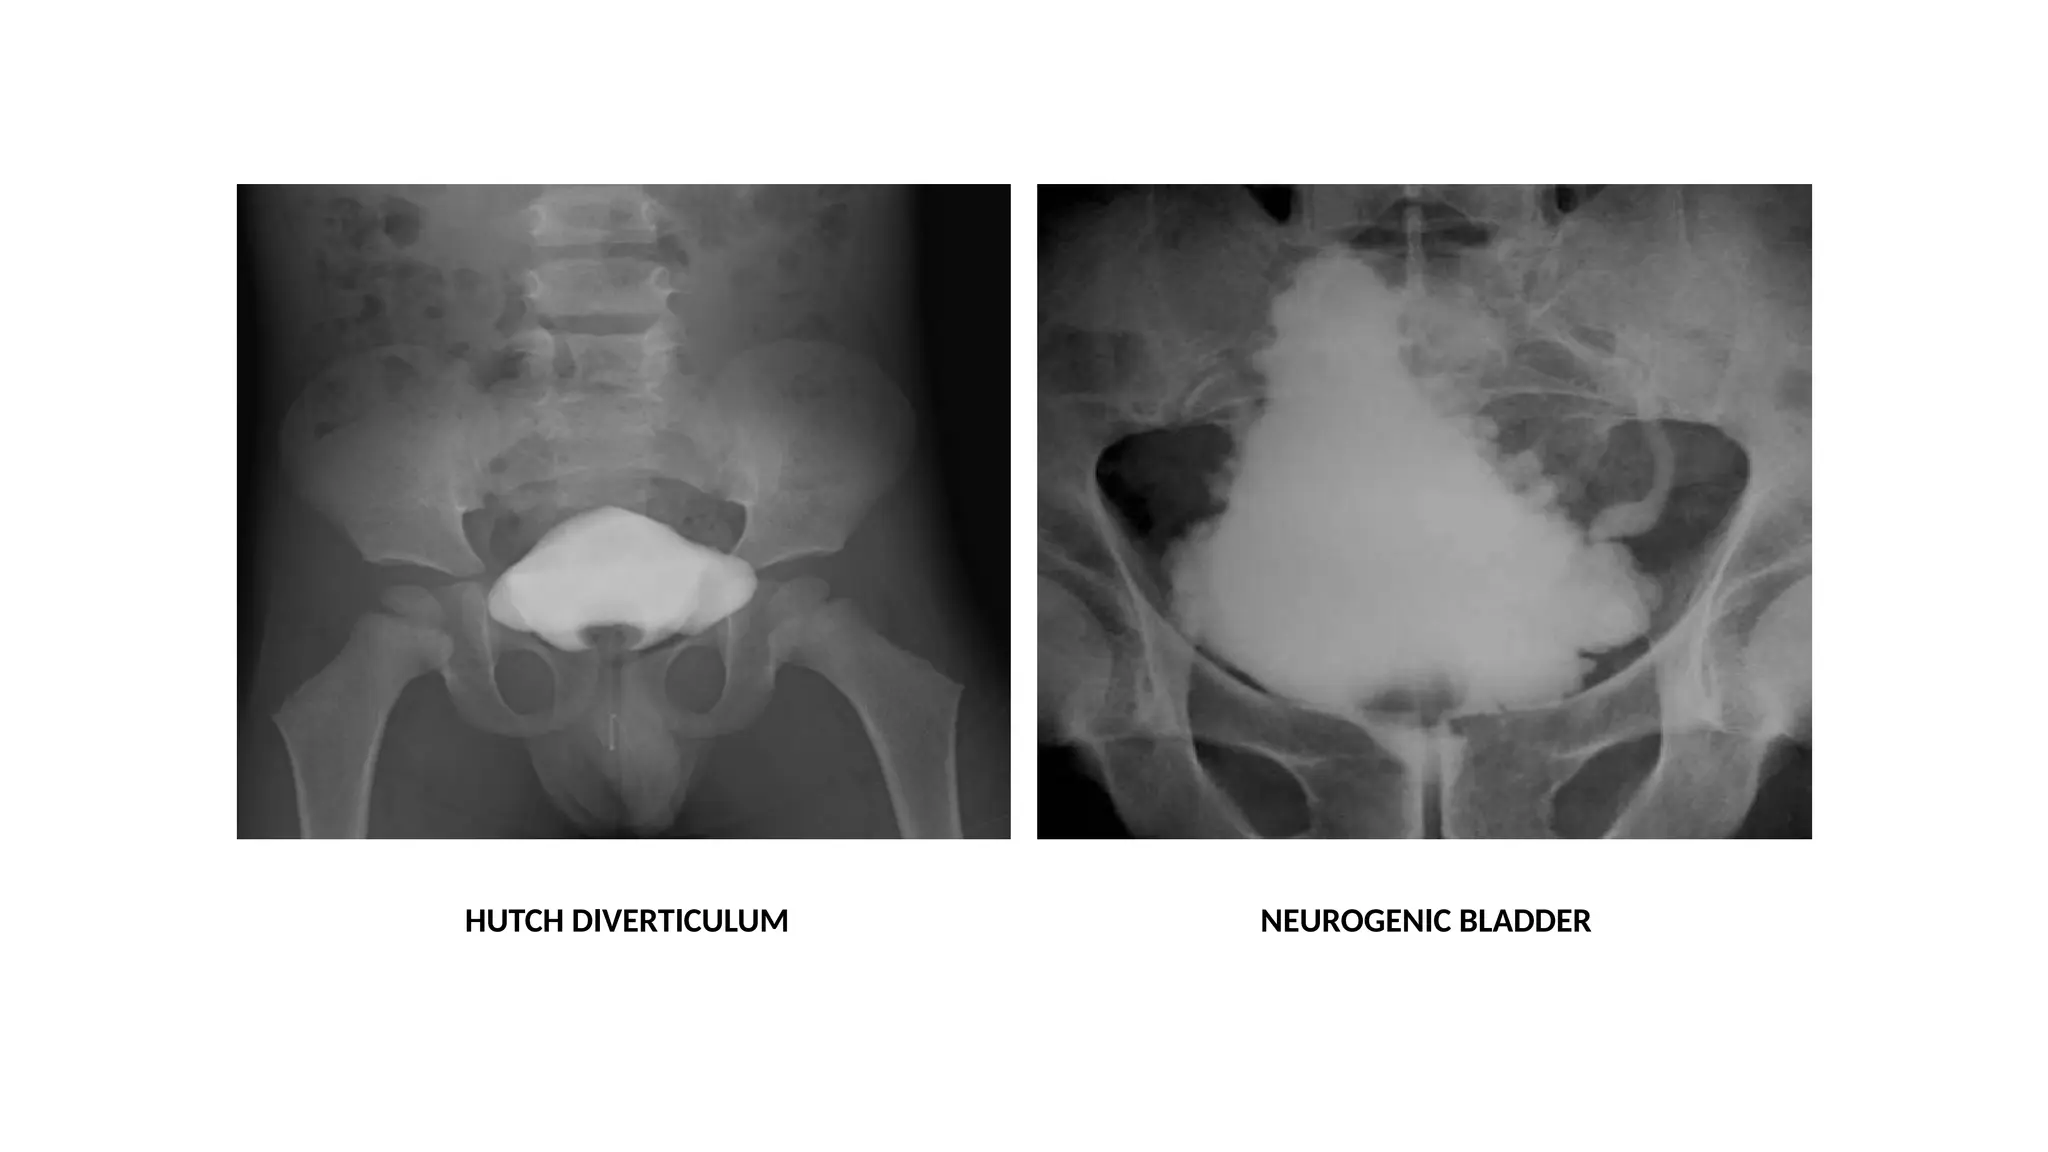

HUTCH DIVERTICULUM NEUROGENIC BLADDER

• #29 Voiding cyctourethrography in AP and oblique projections sowing bladder diverticulum